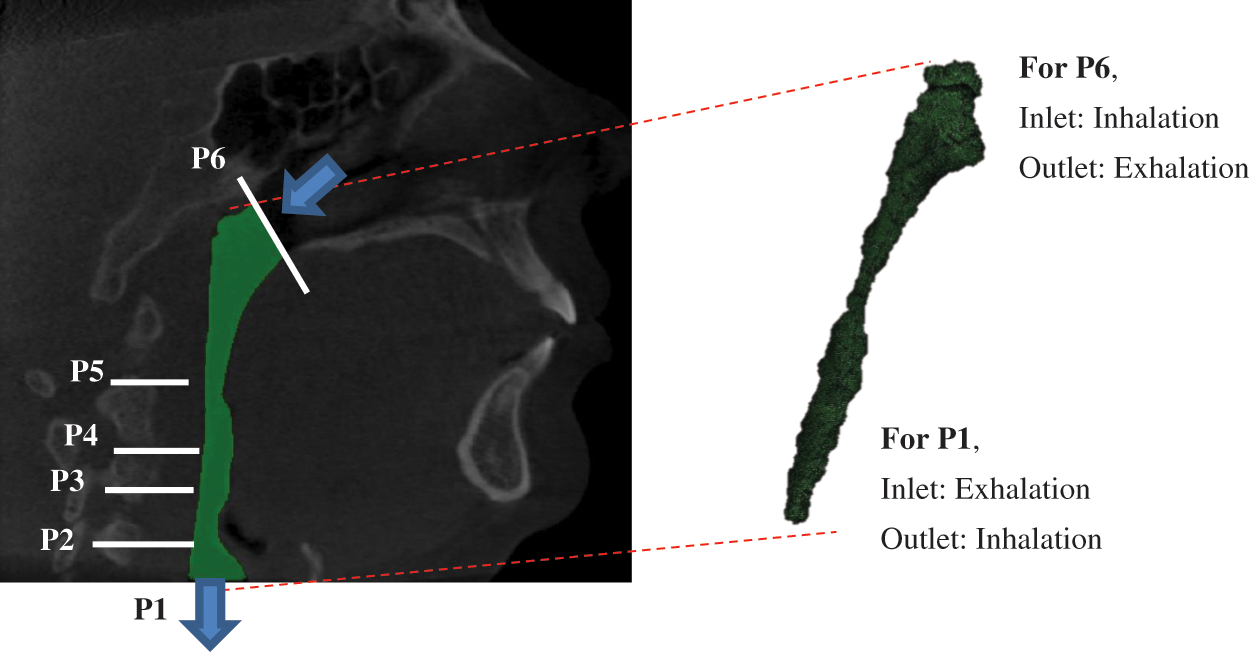

2 Method to Study the Human Upper Airway

The method used in this work includes CFD modelling and segmentation of computed tomography scan (CT scan) acquisition, which has been described and explained in previous research [1]. Therefore, Fig. 1 portrays the CFD modelling in which the model was a segmentation of the pharyngeal in the human upper airway. The volume of the model was created based on real patient computed tomography (CT) images. The focus was on both flow simulations. Thus, the marked locations of P6 and P1 are defined as the inlet and outlet boundary conditions for inhaling, but for exhaling, P6 is defined as outlet and P1 as an inlet. The TKE in the upper airway was obtained in the simulation by considering all essential parameters and boundary conditions adopted in previous research.

Figure 1: Breathing condition for inhaling and exhaling for OSA patient